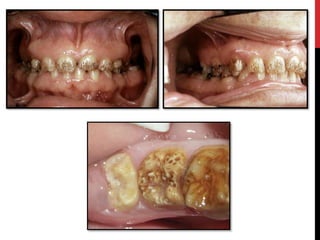

• #28 Hypoplastic amelogenesis imperfecta: Basic alteration centers on inadequate deposition of enamel matrix. Generalized pattern: Pin point to pin head sized pits are scattered across the surface of the teeth. The buccal surface of the teeth are affected more severely and the pits are arranged in rows or columns. Staining of the pits may occur. The enamel between pits is of normal thickness, hardness and coloration.

• #30 Localized pattern The affected teeth demonstrates horizontal rows of pits,a linear depression,or one large area of hypoplastic enamel surrounded by a zone of hypocalcification. Altered area is located in the middle third of the buccal surfaces of the teeth.The incisial third or occlusal surfaces is not affected. Both the dentitions are affected.The autosomal recessive type is more severe and typically demonstrates involvement of all teeth in both the dentitions.

• #31 Autosomal dominant smooth pattern: The enamel of all teeth exhibits a smooth surface and is thin hard and glossy. The absence of appropriate enamel thickness results in teeth that are shaped like crown preparations and demonstrate open contact points. The color of teeth varies from opaque white to translucent brown. Radiographically the teeth exhibit a thin peripheral outline of radiopaque enamel.

• #32 X-linked smooth pattern Exhibits diffuse thin, smooth, and shiny enamel in both dentitions. The teeth often have the shape of crown preparations,and the contacts points open. The color varies from brown to yellow-brown. Radiographs show a peripheral outline of radioopaque enamel.unerupted teeth undergo resorption. An open bite is seen in almost all males and in a minority of females. X-linked rough pattern The enamel is thin, hard and rough surfaced.As in smooth forms, the teeth taper towards the incisial occlusal surface and demonstrate open contact points. The color varies from white to yellow white. The enamel is denser than that seen in smooth patterns and the teeth are less vulnerable to attrition. Radiographs exhibit a thin peripheral outline of radio dense enamel.

• #33 The enamel is softer than normal and tends to chip of from the underlying dentin. Radiographically the affected enamel exhibits a radiodensity that is similar to dentin.

• #34 Pigmented pattern The surface enamel is mottled and agar brown. The enamel often fractures from the underlying dentin. Anterior open bite and unerupted teeth exhibiting resorption are common.

• #35 X linked pattern The affected males exhibits different patterns in the deciduous and permanent dentitions. The deciduous teeth are opaque white with a translucent mottling, the permanent teeth are opaque yellow white and may darken with age.

• #37 Snow capped patterns Exhibit a zone of white opaque enamel on the incisal or occlusal one third of the crown. The affected teeth often demonstrates an anterior to posterior distribution .Both the dentitions are affected.